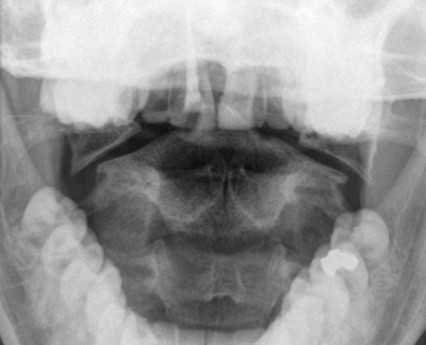

Перелом С1 Джефферсона. Рентгенография через открытый рот. С обеих сторон расширено расстояние от нижних площадок ножек С2 до боковых масс С1. Боковые массы С1 смещены латерально и перестают быть в линию с боковыми массами С1.

Обследование начинается со стандартной рентгенографии в 3 проекциях - боковой, передне-задней (прямой) и через рот.